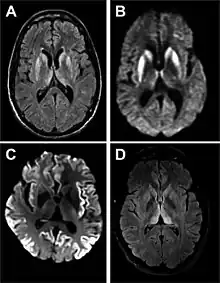

- MRI with diffusion weighted inversion (DWI) and fluid-attenuated inversion recovery (FLAIR) shows a high signal intensity in certain parts of the cortex (a cortical ribboning appearance), the basal ganglia, and the thalami.[36] The most common presenting patterns are simultaneous involvement of the cortex and striatum (60% of cases), cortical involvement without the striatum (30%), thalamus (21%), cerebellum (8%) and striatum without cortical involvement (7%). In populations with a rapidly progressive dementia (early in the disease process), MRI has a sensitivity of 91% and specificity of 97% for diagnosing CJD.[43] The MRI changes characteristic of CJD may also be seen in the immediate aftermath (hours after the event) of autoimmune encephalitis or focal seizures.[36]

Imaging

Imaging of the brain may be performed during medical evaluation, both to rule out other causes and to obtain supportive evidence for diagnosis. Imaging findings are variable in their appearance, and also variable in sensitivity and specificity.[46] While imaging plays a lesser role in diagnosis of CJD,[47] characteristic findings on brain MRI in some cases may precede onset of clinical manifestations.[48]

Brain MRI is the most useful imaging modality for changes related to CJD. Of the MRI sequences, diffuse-weighted imaging sequences are most sensitive.[49] Characteristic findings are as follows:

- Focal or diffuse diffusion-restriction involving the cerebral cortex and/or basal ganglia. The most characteristic and striking cortical abnormality has been called "cortical ribboning" or "cortical ribbon sign" due to hyperintensities resembling ribbons appearing in the cortex on MRI.[50] The involvement of the thalamus can be found in sCJD, is even stronger and constant in vCJD.[51]

- Varying degree of symmetric T2 hyperintense signal changes in the basal ganglia (i.e., caudate and putamen), and to a lesser extent globus pallidus and occipital cortex.[47]